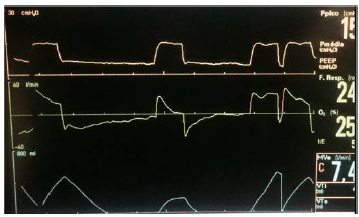

Uma paciente de 58 anos de idade encontra-se mantido em ventilação mecânica invasiva. As curvas do ventilador são as demonstradas na imagem apresentada.

Uma forma adequada de tentar corrigir tal assincronia seria a(o)

Qual a assincronia demonstrada?

Assinale a alternativa que indica a ciclagem nesse ajuste de ventilação.

Qual o modo ventilatório?

A variável limite dessa ventilação é